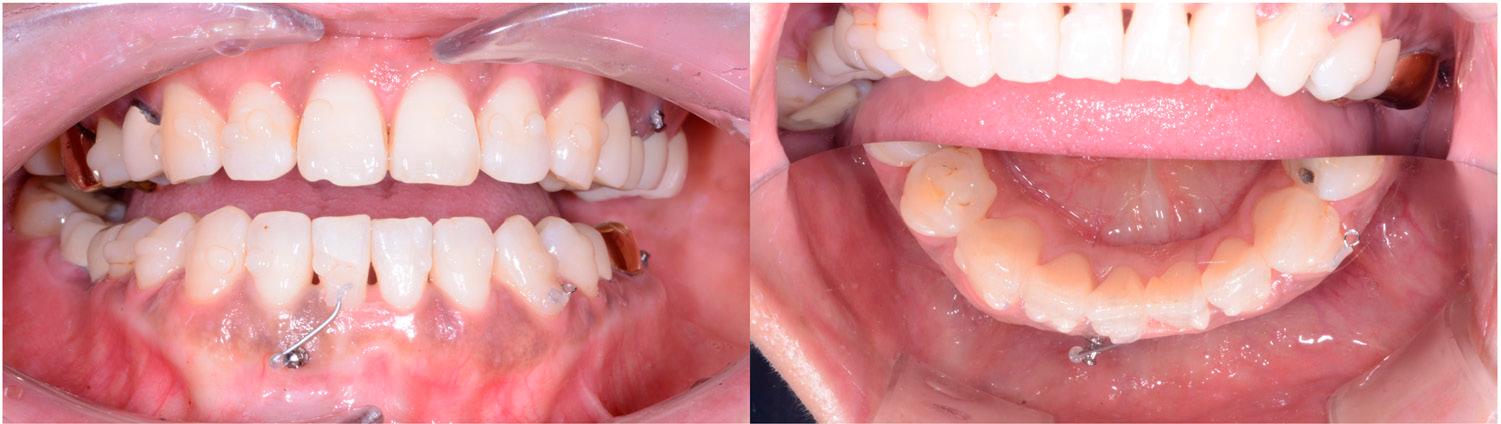

Figure 7.

Figure 8.